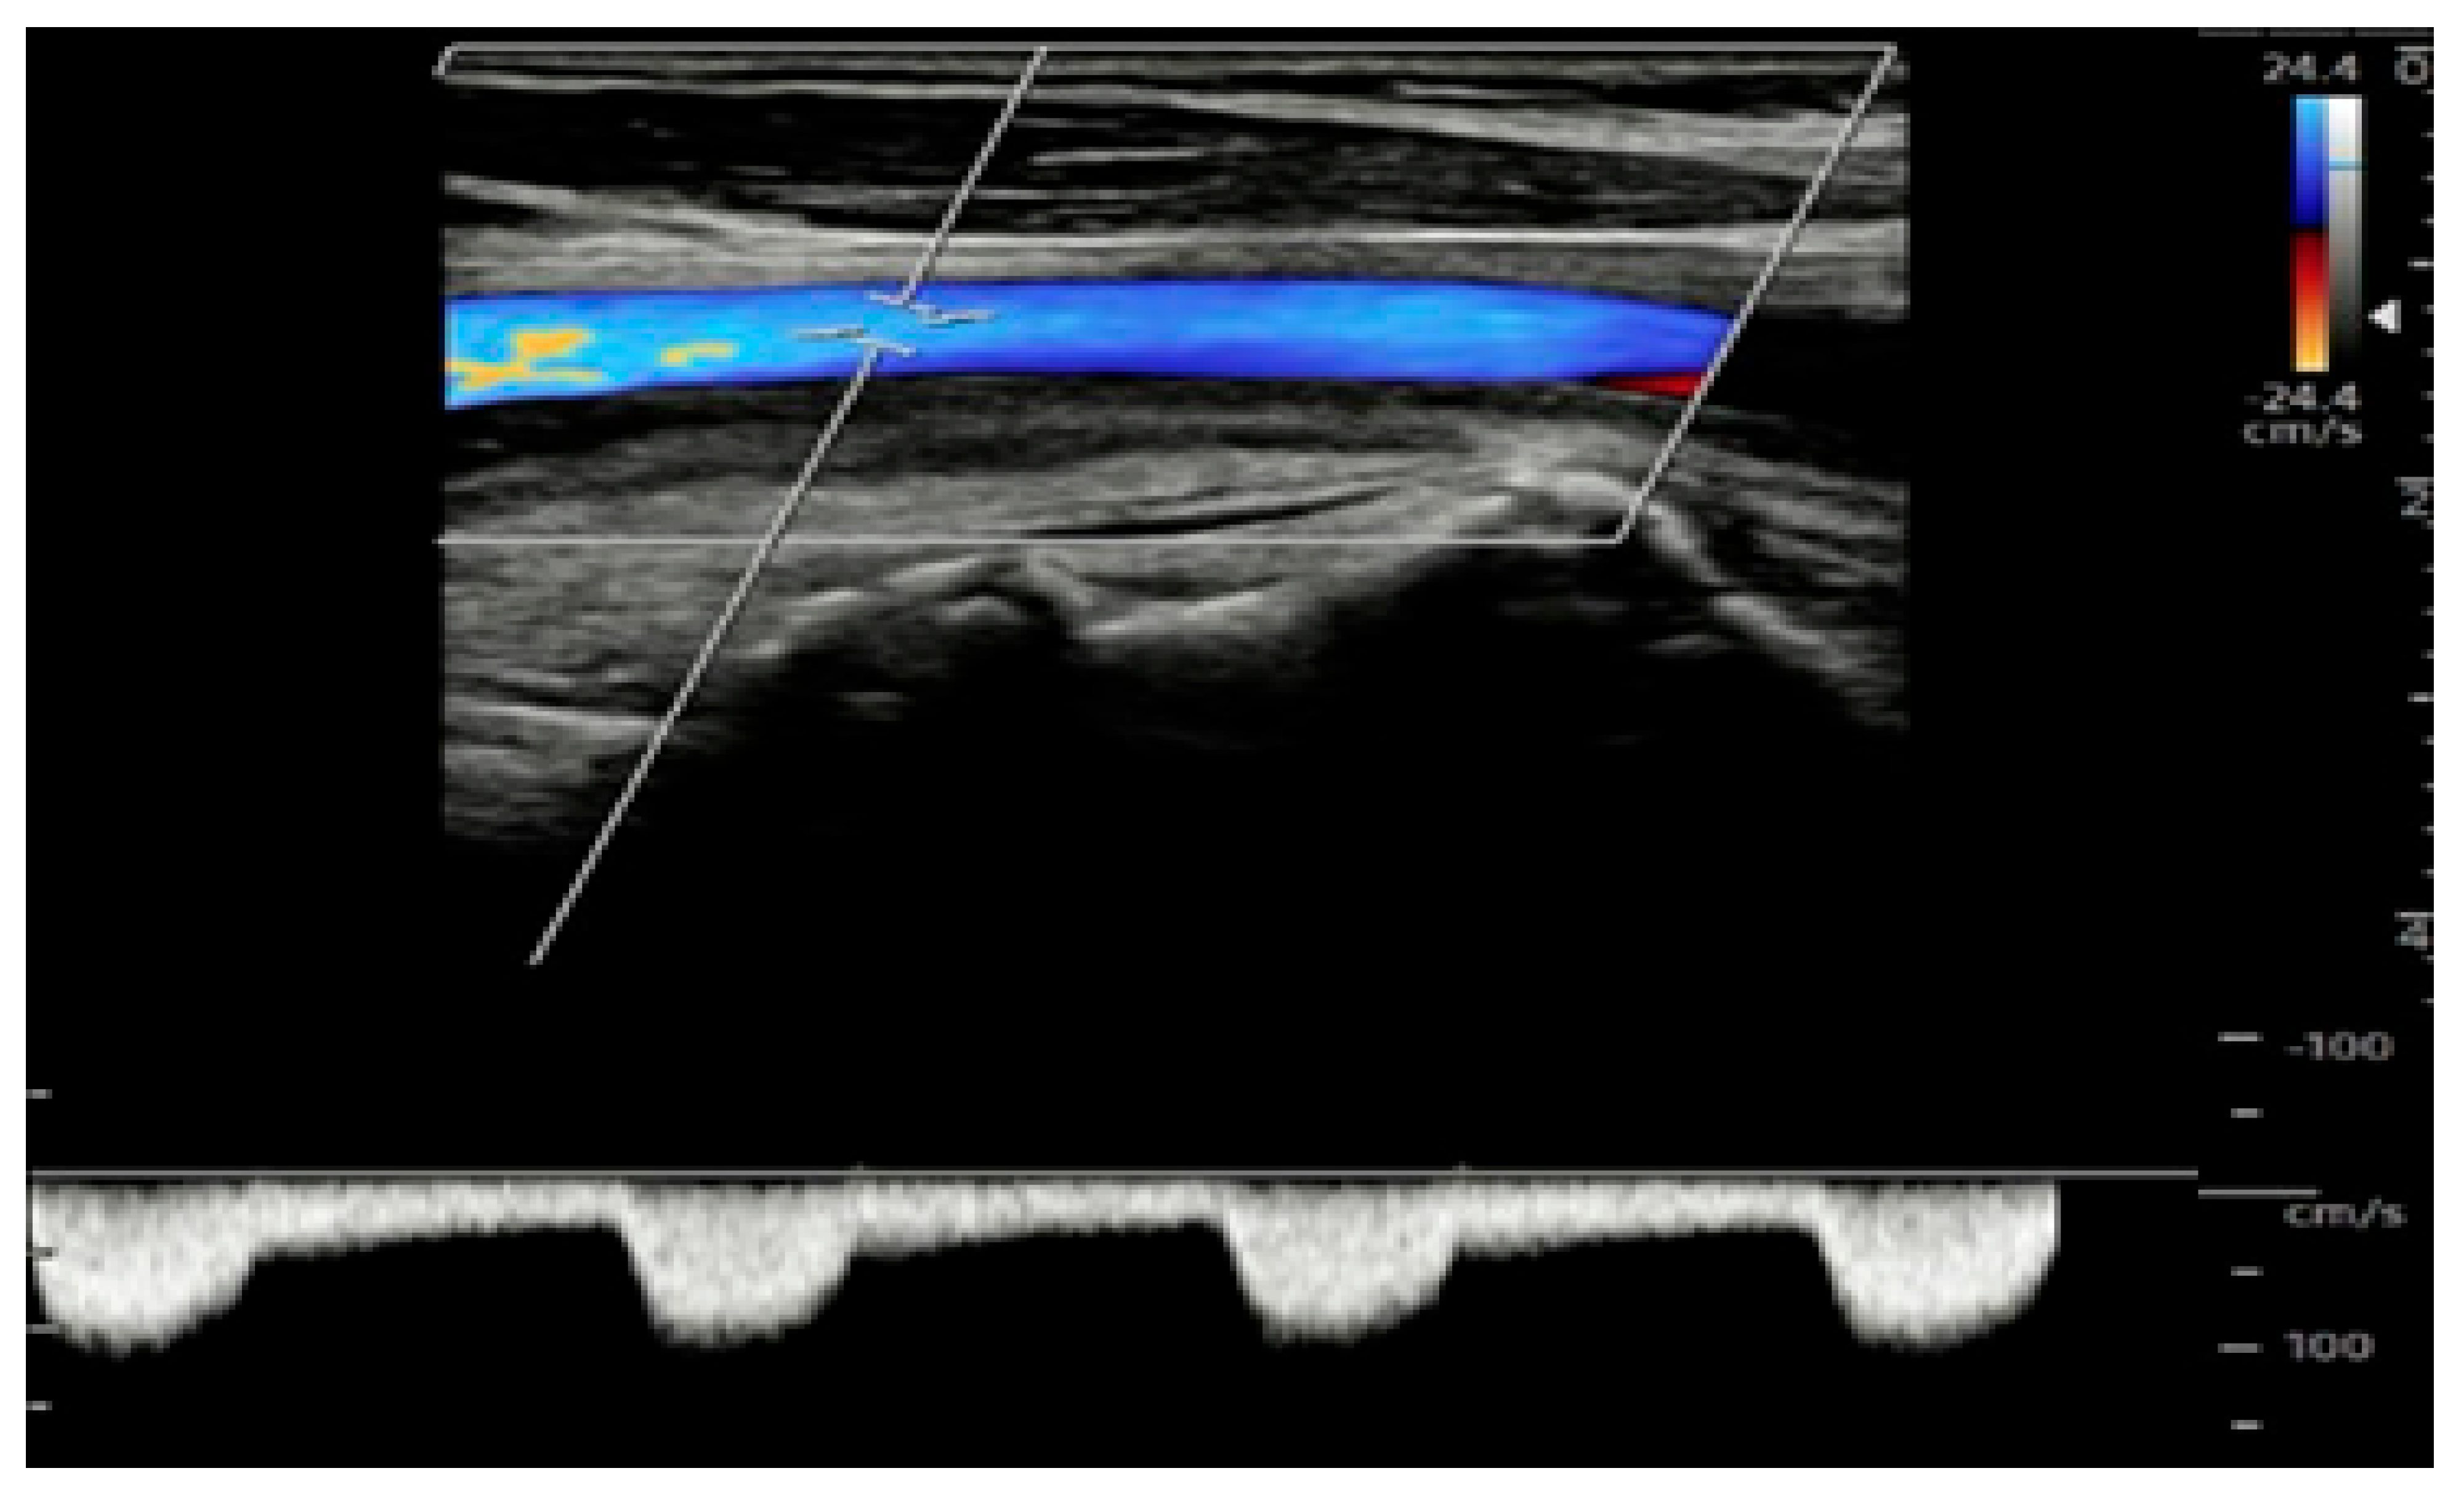

Extended Color Doppler Ultrasound in the Diagnosis of Giant Cell Arteritis: Clinical Insights and Literature Review with Emphasis on Posterior Circulation Involvement

- The use of extended CDUS protocols, including assessment of temporal, axillary, subclavian, carotid and vertebral arteries.

- Kargiotis, O.; Psychogios, K.; Safouris, A.; Bakila, E.; Andreadou, E.; Karapanayiotides, T.; Finitsis, S.; Palaiodimou, L.; Giannopoulos, S.; Magoufis, G.; et al. Cervical duplex ultrasound for the diagnosis of giant cell arteritis with vertebral artery involvement. J. Neuroimaging 2021, 31, 656–664. [Google Scholar] [CrossRef]